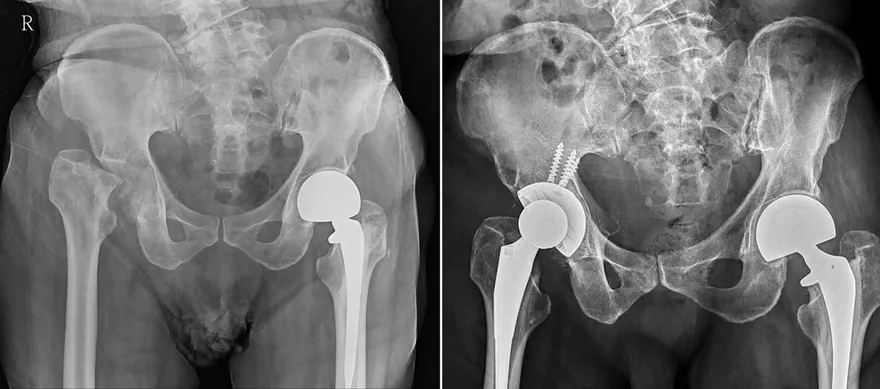

退化性關節炎

人工膝關節置換

膝蓋退化

膝蓋受損

雙膝置換

骨科

大甲李綜合醫院

膝關節磨損